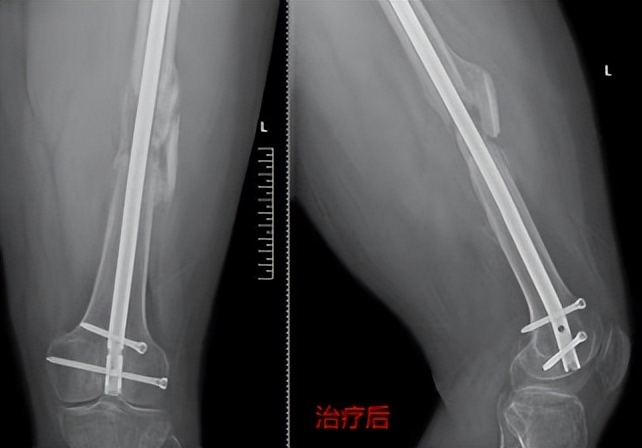

骨干骨折术后骨不愈合

患者袁某,男,22岁,正值风华正茂的年龄,不幸的是1年前因车祸致左股骨干粉碎性骨折,在当地医院行切开复位髓内钉内固定术,术后伤口愈合良好,患者满怀希望疾病早点康复,早点回学校读书,但随着术后的每一次复查,都是一次次的打击,因为每次复查都没有发现骨折愈合迹象,且在术后一年的时候出现了更不好的是股骨髓内钉近端锁定钉断裂,到省级多家医院求医,给的治疗方案都是手术植骨治疗,患者及家人都十分焦急,经多方打听,慕名来到郑州市骨科医院骨病·骨肿瘤科I找到王顺利主任,王主任详细询问病史及阅片后,告诉患者可以行骨伤病最新绿色疗法冲击波保守治疗,不用手术植骨治疗,并为患者制定了个性化治疗方案,袁某非常高兴并满怀信心告诉王主任一定配合治疗,经过三个疗程的冲击波治疗股骨干骨折愈合了。